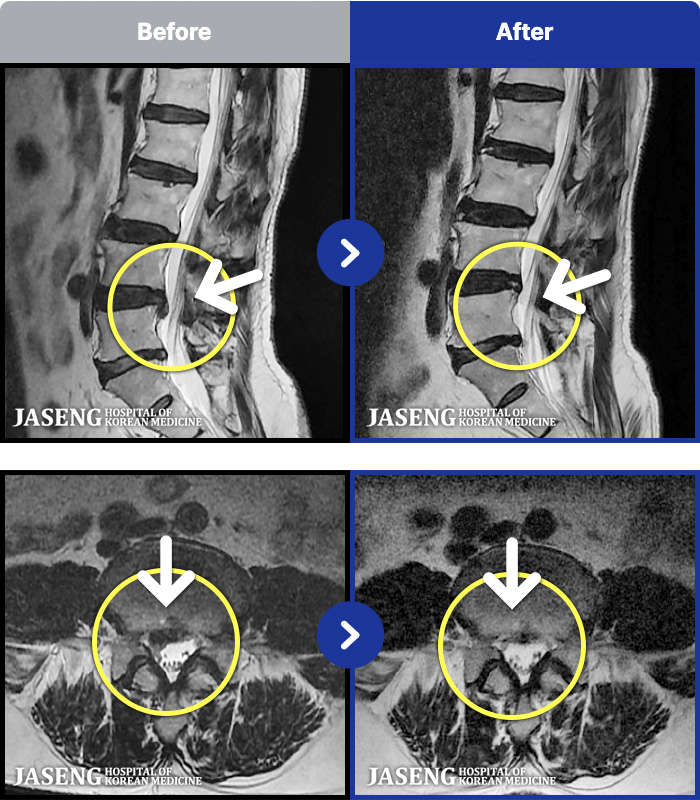

1,257 MRI ũ ʸ Ȯϼ.